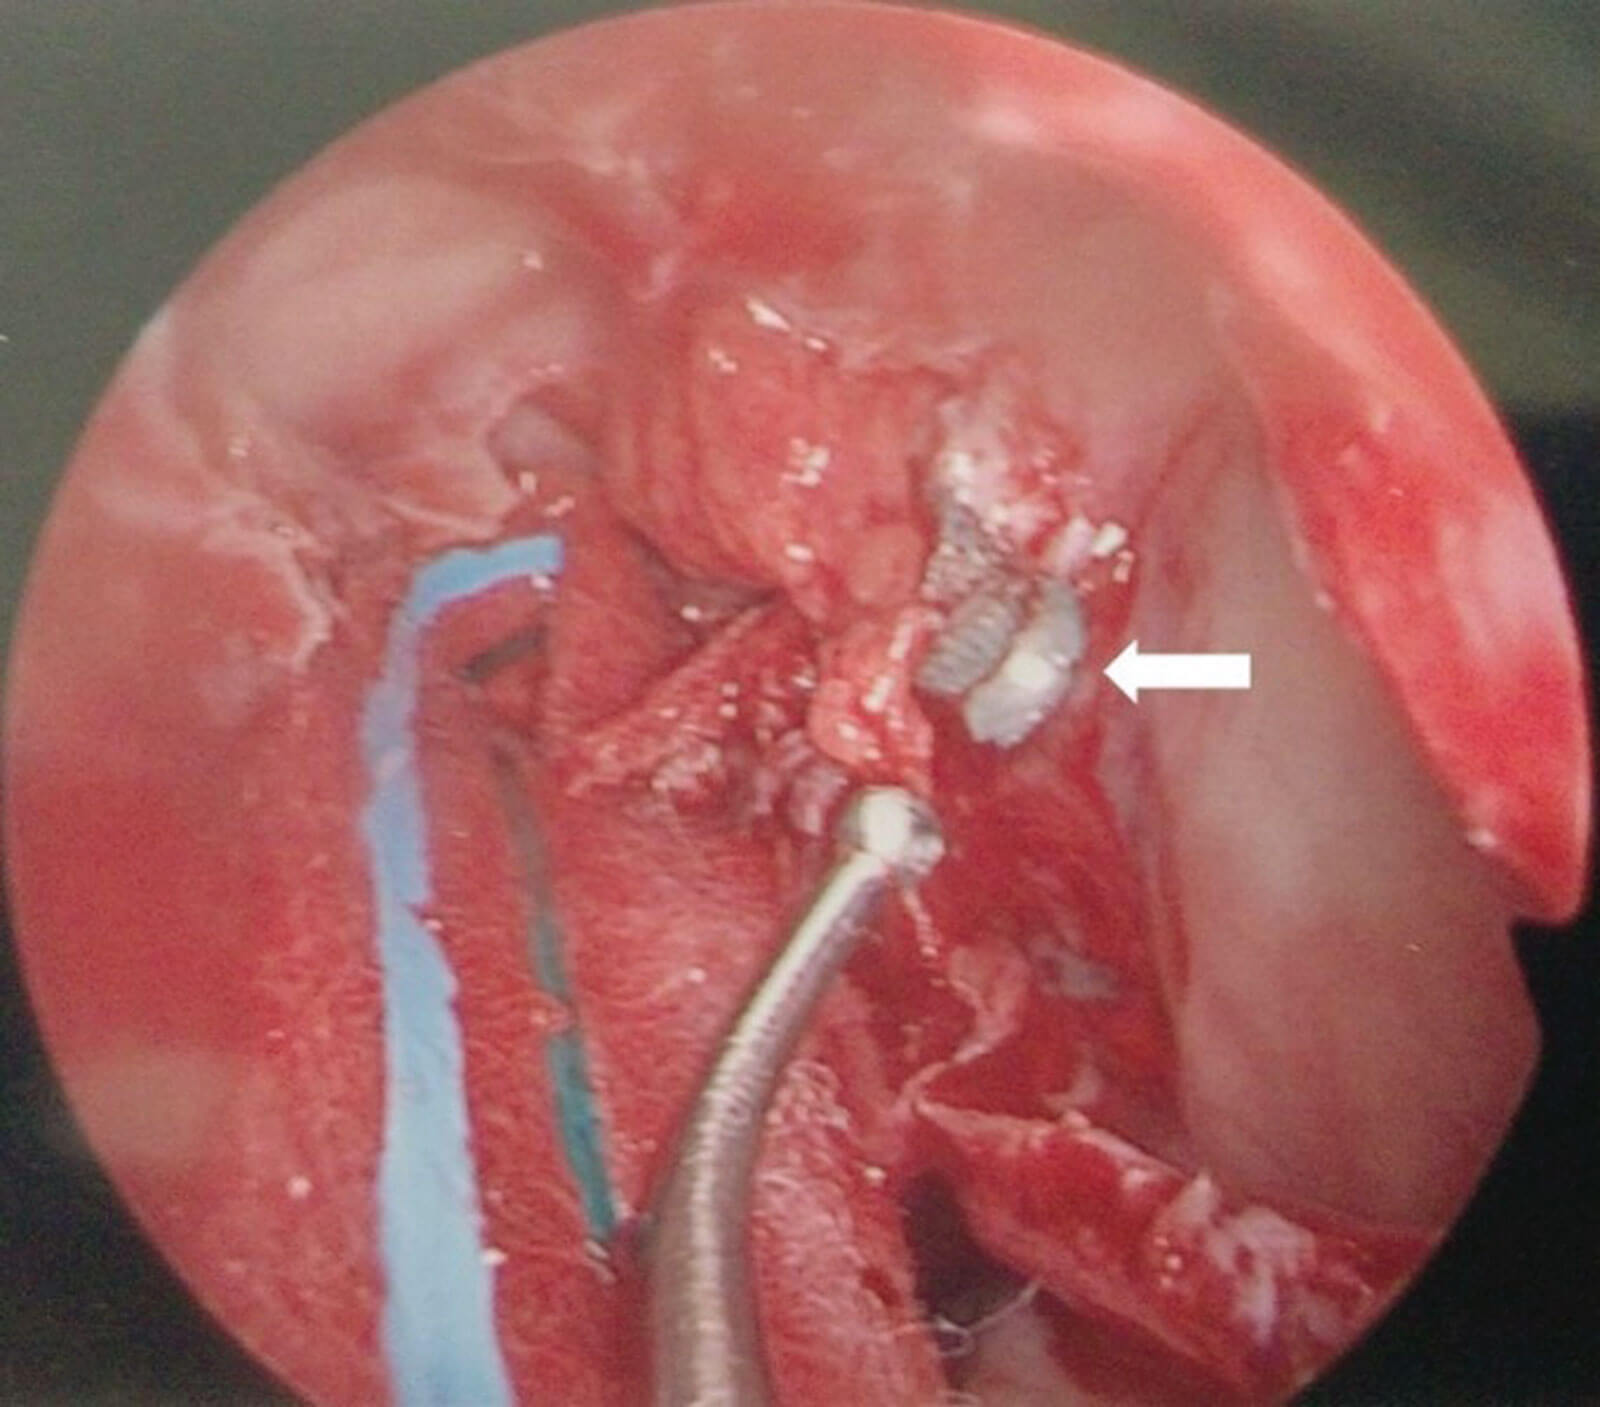

Figure 2: Left transnasal endoscopic view showing the airgun pellet located in the orbital apex.

Traditional approaches to the orbital apex are via a lateral orbitotomy however, FB within the medial intraconal space can be approached endoscopically. Retrobulbar objects pose unique surgical challenges and only a few have reported on removal using endoscopic approaches using a minimally invasive corridor to approach [6,7]. Intraconal FB are especially difficult to visualise within orbital fat and image guided navigation is essential for accurate localisation before mobilisation of orbital fat. Pellets tend to migrate whilst being manipulated during retrieval and success requires an advanced skill set (Figure 2). If ferrous, an endoscopic magnetic-assisted approach has been described [8].